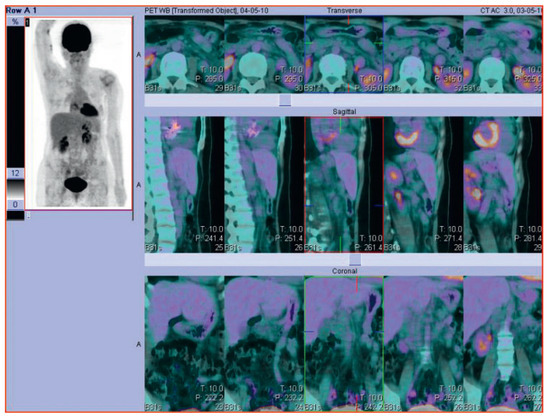

Cardiac complications in a patient with Hodgkin lymphoma—a case report

Figure 2. Follow-up PET-CT scan of the same patient with Hodgkin Lymphoma after successful treatment.